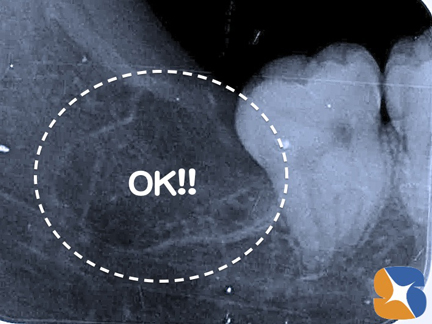

横向きの親知らずDr:「完全に横向きに生えていますね。レントゲンの結果、親知らずより一つ手前の歯は、まだ虫歯になっていません。将来的に親知らずと接触している部分から虫歯になる可能性がありますので、迷わず今、抜いておくべきだと思います。」

横向きの親知らず 2分割横向きの歯を抜歯する場合はこのように、歯を2分割します。この患者様の場合、かなり根っこが湾曲しており、「難抜歯」と予測されましたので、点滴をしながらの抜歯の選択は、とても良かったと思われます。